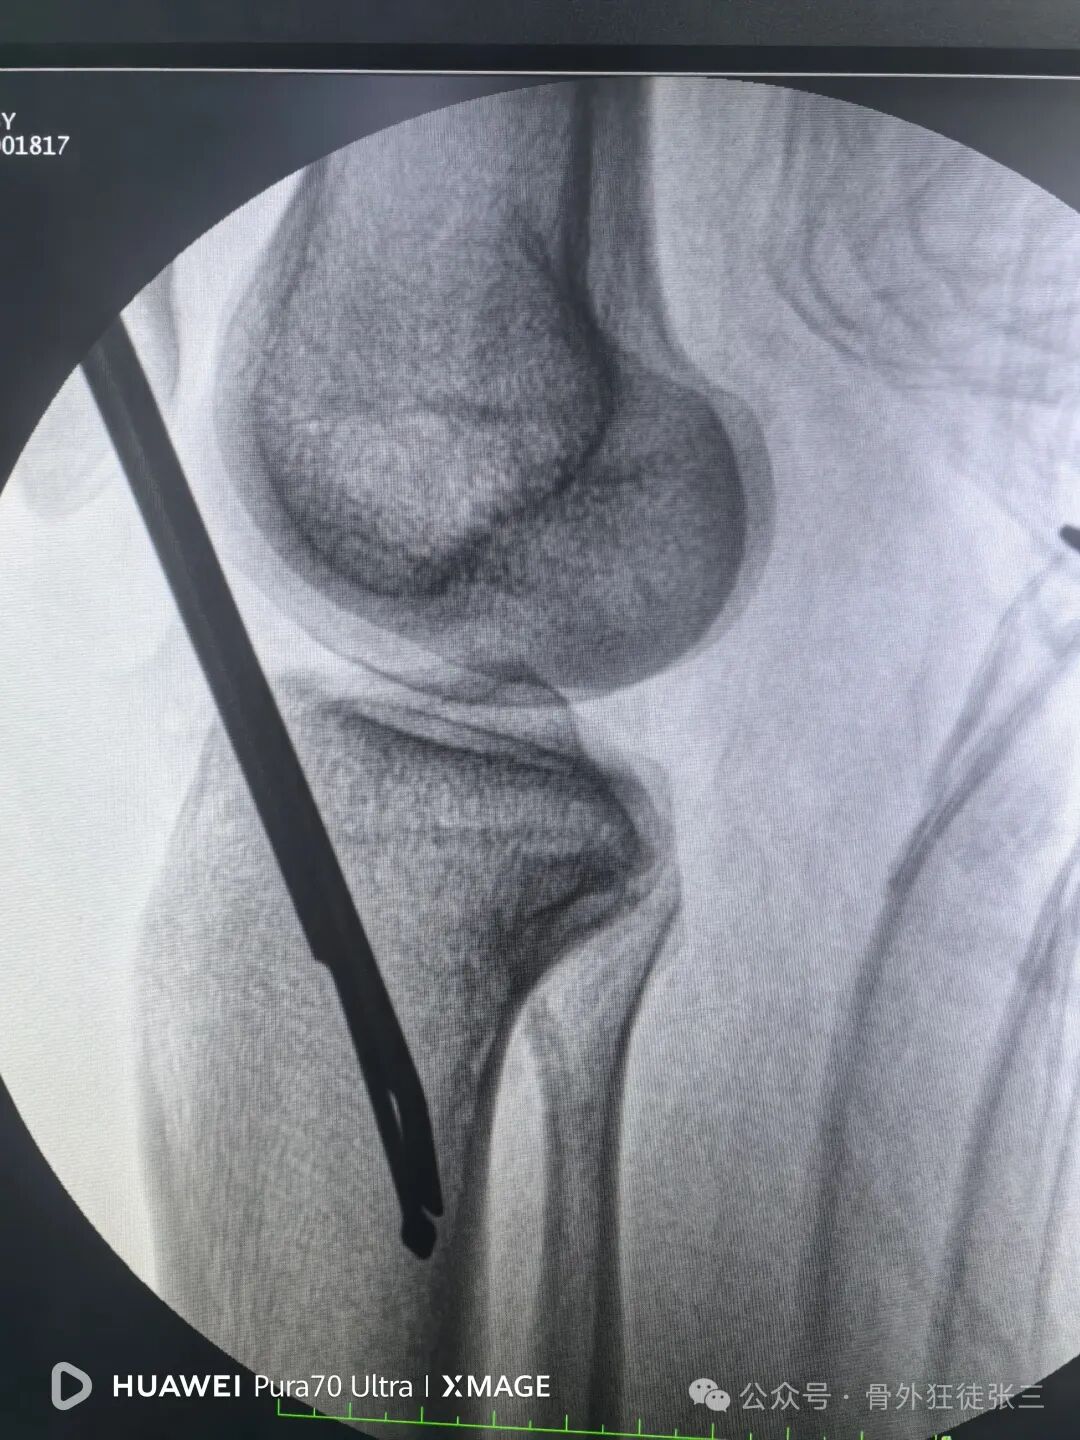

侧位复位良好

踝关节侧位钉子长度满意,居中